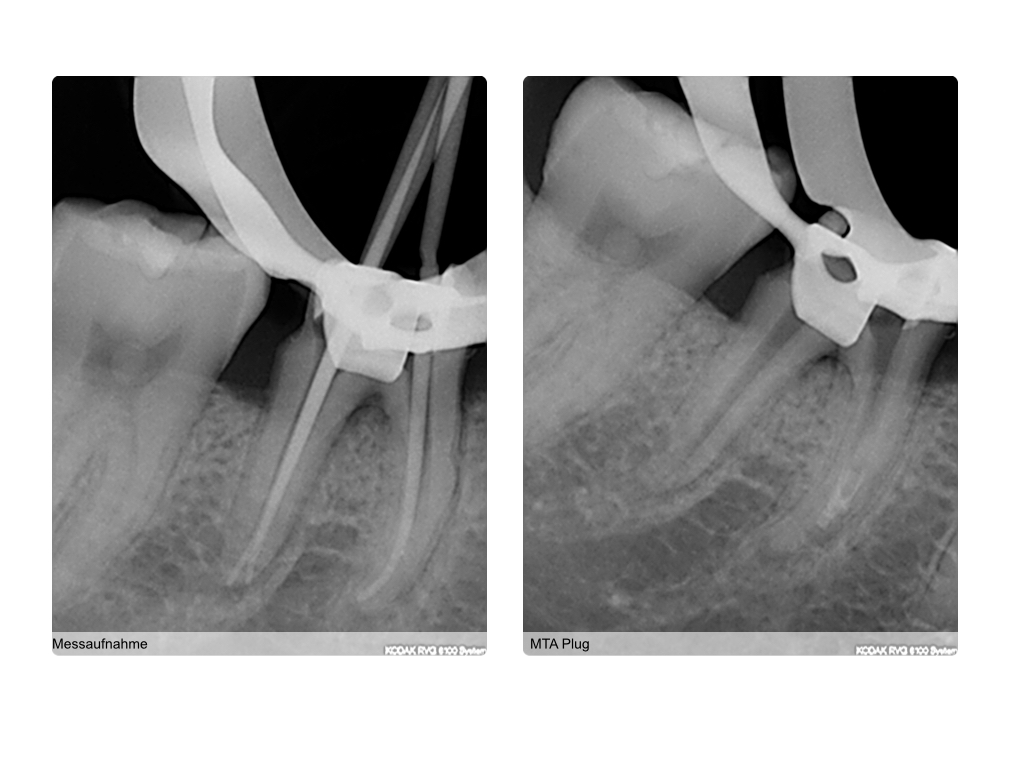

Saving hopeless teeth (36)